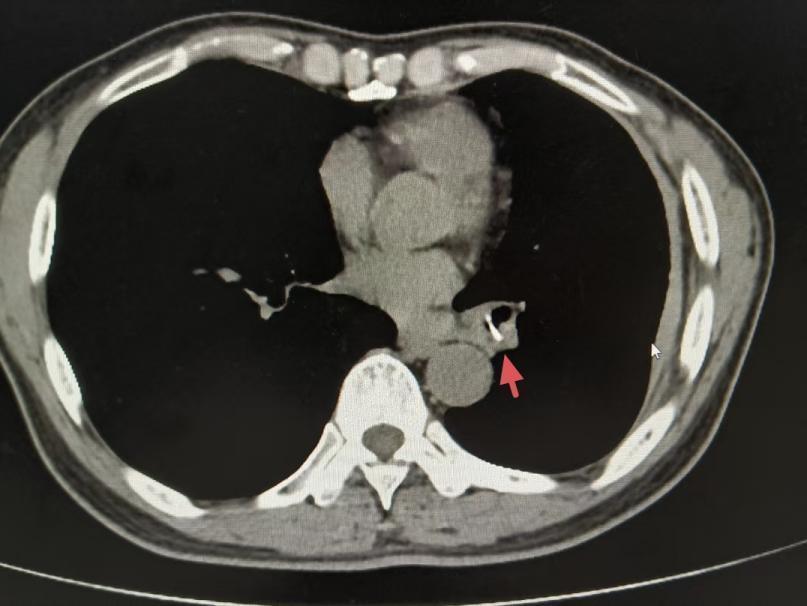

在市十二医院再次接受的胸部CT结果显示,陈叔左下肺支气管有可疑异物影像。追问病史时,陈叔回忆起一年前吃鱼时曾有剧烈呛咳史,但当时症状自行缓解,该院呼吸科副主任医师陈子谓敏锐地捕捉到了这一关键信息,随后的纤维支气管镜检查也印证了他的猜想。镜下清晰可见一块疑似骨头的异物嵌顿于左下肺支气管,周围组织已形成化脓性炎症。困扰陈叔一年多的罪魁祸首终于现形。

左下肺支气管可疑异物影像